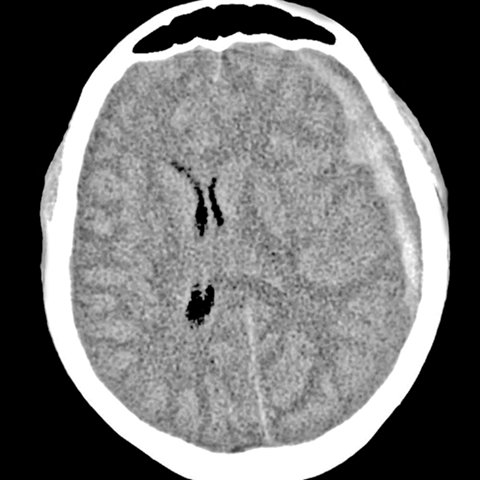

Subdural Hematoma [1 of 3]